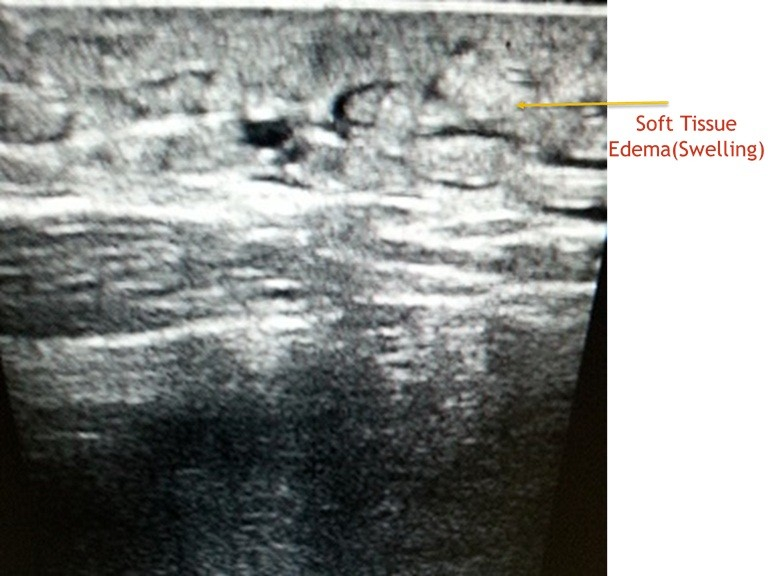

Till i spoke to him ,i thought he had a common easily curable illness.I learnt from him that ,in last 3 months he consulted 2 doctors,one of them a surgeon with no respite.One had treated him empirically and while  the other had referred him to a vascular surgeon,specialist dealing with blood vessels of legs .The vascular surgeon rightly requested a blood vessel study(Doppler ultrasound test)of the leg.I did a detailed examination of veins and arteries of the leg and found them normal.And  radiologists do not stop till they unearth the mystery of diagnosis.I gently interrogated his abdomen with ultrasound.I was not happy with what i found.It was a  dangerous tumour (sarcoma )involving muscles and deep structures of abdomen(retro peritoneum)impeding the fluid flow from leg and hence causing its swelling. Had the radiology scan been performed earlier,delay in diagnosis could have been avoided.